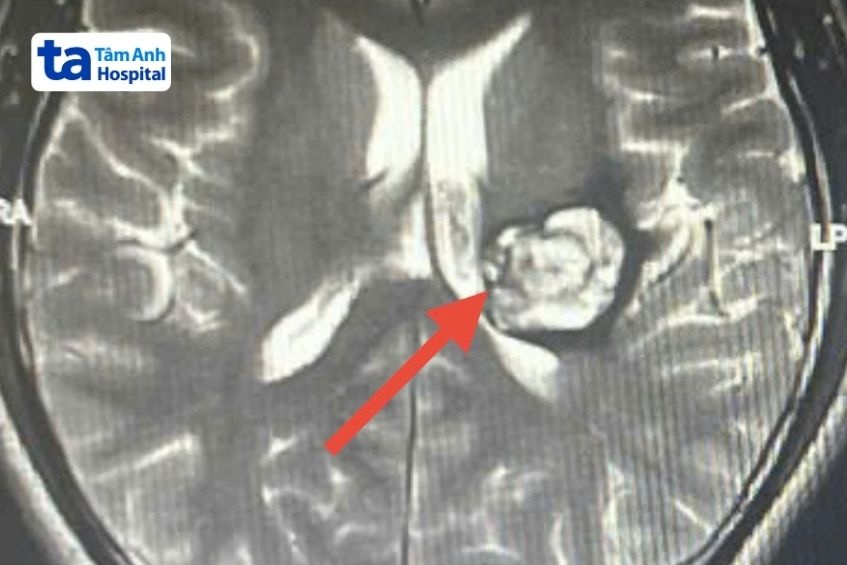

Ngày 24/12, ThS.BS.CKII Mai Hoàng Vũ, Khoa Phẫu thuật Thần kinh, Bệnh viện Đa khoa Tâm Anh TP HCM, cho biết kết quả chụp MRI 3 Tesla tại xác định anh Tú mắc khối u mạch máu thể hang tại vùng đồi thị bên trái, kích thước 3×3 cm, đã chảy máu bên trong u.

Đồi thị nằm sâu trong đại não, đóng vai trò quan trọng như trạm trung chuyển các xung động thần kinh từ các sợi thần kinh chuyển đến, sau đó tiếp tục chuyển đến vỏ não. Đây còn là nơi tận cùng của các sợi thần kinh vận động thuộc hệ ngoại tháp và chứa nhiều nhân quan trọng của hệ thần kinh. Bất kỳ tổn thương nào tại vị trí đồi thị đều rất nguy hiểm, thậm chí khiến người bệnh tử vong.

“Tình trạng chảy máu bên trong nhiều lần khiến u tăng nhanh kích thước, nguy cơ vỡ đột ngột, dẫn đến chảy máu sâu trong đại não trái, đột quỵ xuất huyết não”, bác sĩ Vũ cho biết, thêm rằng nếu không mổ người bệnh nguy cơ tử vong cao hoặc di chứng khiếm khuyết chức năng thần kinh vận động và ngôn ngữ. Hiện sức cơ nửa người phải của anh Tú đã giảm 50%, nói khó.